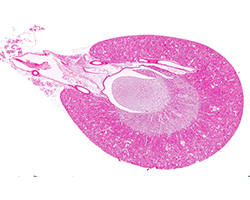

Genital Masculino

Genital Masculino

Testículo, epidídimo, conducto deferente, próstata y vesícula seminal.

(8 preparaciones) -